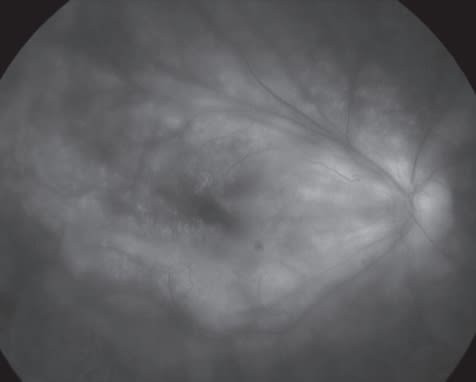

Choroidal involvement in the eyes of lupus patients has been reported, based on ophthalmoscopic, fluorescein angiographic and ICG evaluations.65,68,69 Choroidopathy with multifocal inflammatory lesions, bone spicules with scarring, serous retinal detachments mimicking multifocal central serous retinopathy (see example in Figure 4), or large serous detachments or uveal effusions have been described.

As confusion can result as to whether ocular findings represent the effects of concurrent systemic steroid or intercurrent infections as confounders in an immunocompromised host, prompt diagnosis and appropriate treatment of the underlying lupus vasculopathy is crucial.